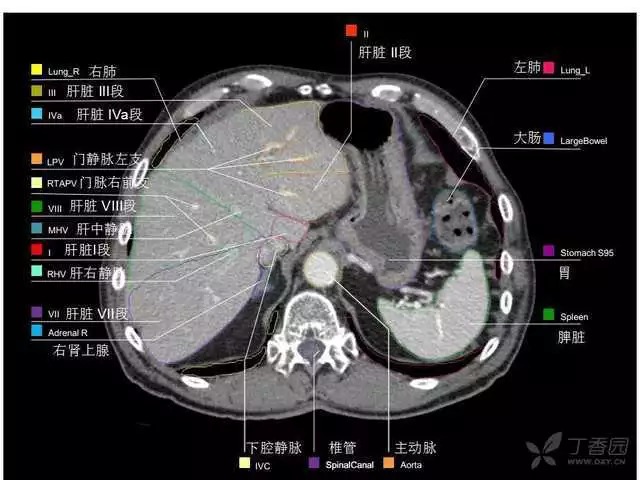

腹部肝脏高清CT断层的图谱

全腹部高清CT图谱,淋巴结彩色图谱,血管解剖图谱大汇总!

超声肝脏分叶及分段

肝脏分段和基本解剖学标志